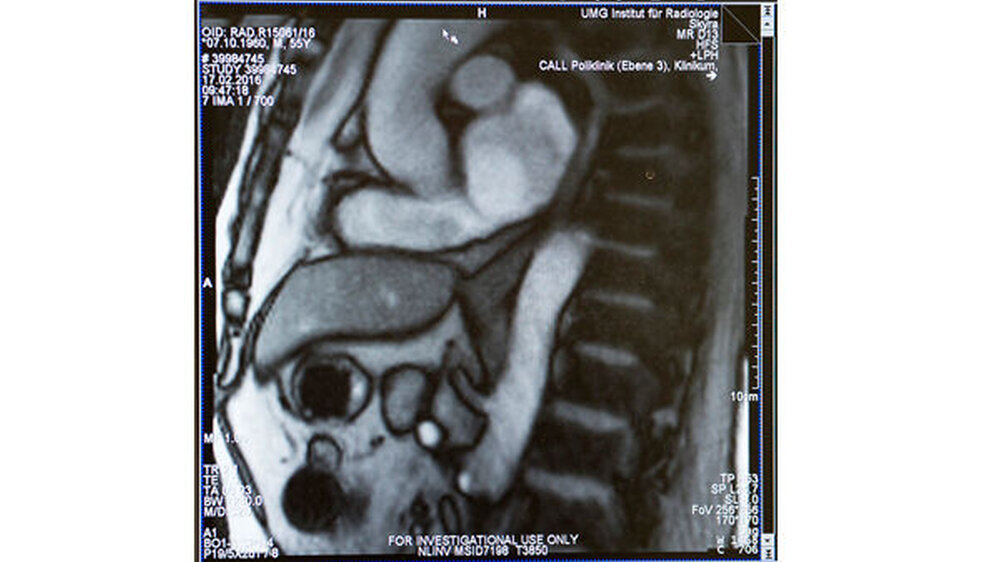

Ein interdisziplinäres Ärzteteam der Universitätsmedizin Göttingen und Forscher des Max-Planck-Instituts für biophysikalische Chemie, Göttingen, haben erstmals den Vorgang des Schluckens mithilfe bildgebender Verfahren dargestellt. Das Forscherteam nutzt dafür das Verfahren der Magnetresonanz-Tomografie (MRT) in Echtzeit. Mit dieser „Echtzeit-MRT“, kann der Schluckakt mit 25 Bildern pro Sekunde dokumentiert und untersucht werden.

Das Echtzeit-MRT liefert Bilder, die für diagnostische Zwecke in der Klinik und für die Behandlung nutzbar sind. Ursachen von Sodbrennen oder Schluckstörungen lassen sich genauer erkennen und untersuchen. Für eine individuelle und gezielte Behandlung der Volkskrankheit Sodbrennen eröffnen sich damit neue Wege.

Die Untersuchung wurde an 24 Patienten durchgeführt.